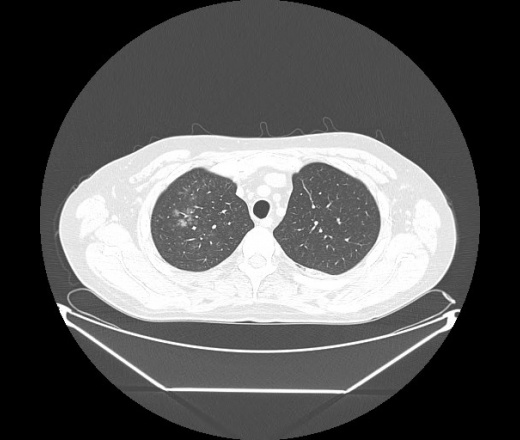

М. 1984 г.р.  Лихорадка 39, кашель , одышка.. и надоевший всем вопрос- "типично ли для ковид?" ( в настоящее время на него обязательно нужно дать ответ в своем протоколе)

На мой взгляд нетипично для ковид: много центрально-расположенных поражений, лобарное поражение нижней доли слева. 50/50

Не типичая картина для ковид.

КТ-признаки двусторонней бактериальной пневмонии.

Все верно, здесь абсолютно нетипичная картина, несмотря на матовое стекло с ретикулярными изменениями, но почему-то  посчитали иначе. Кстати,  "малыша" не заметили)?